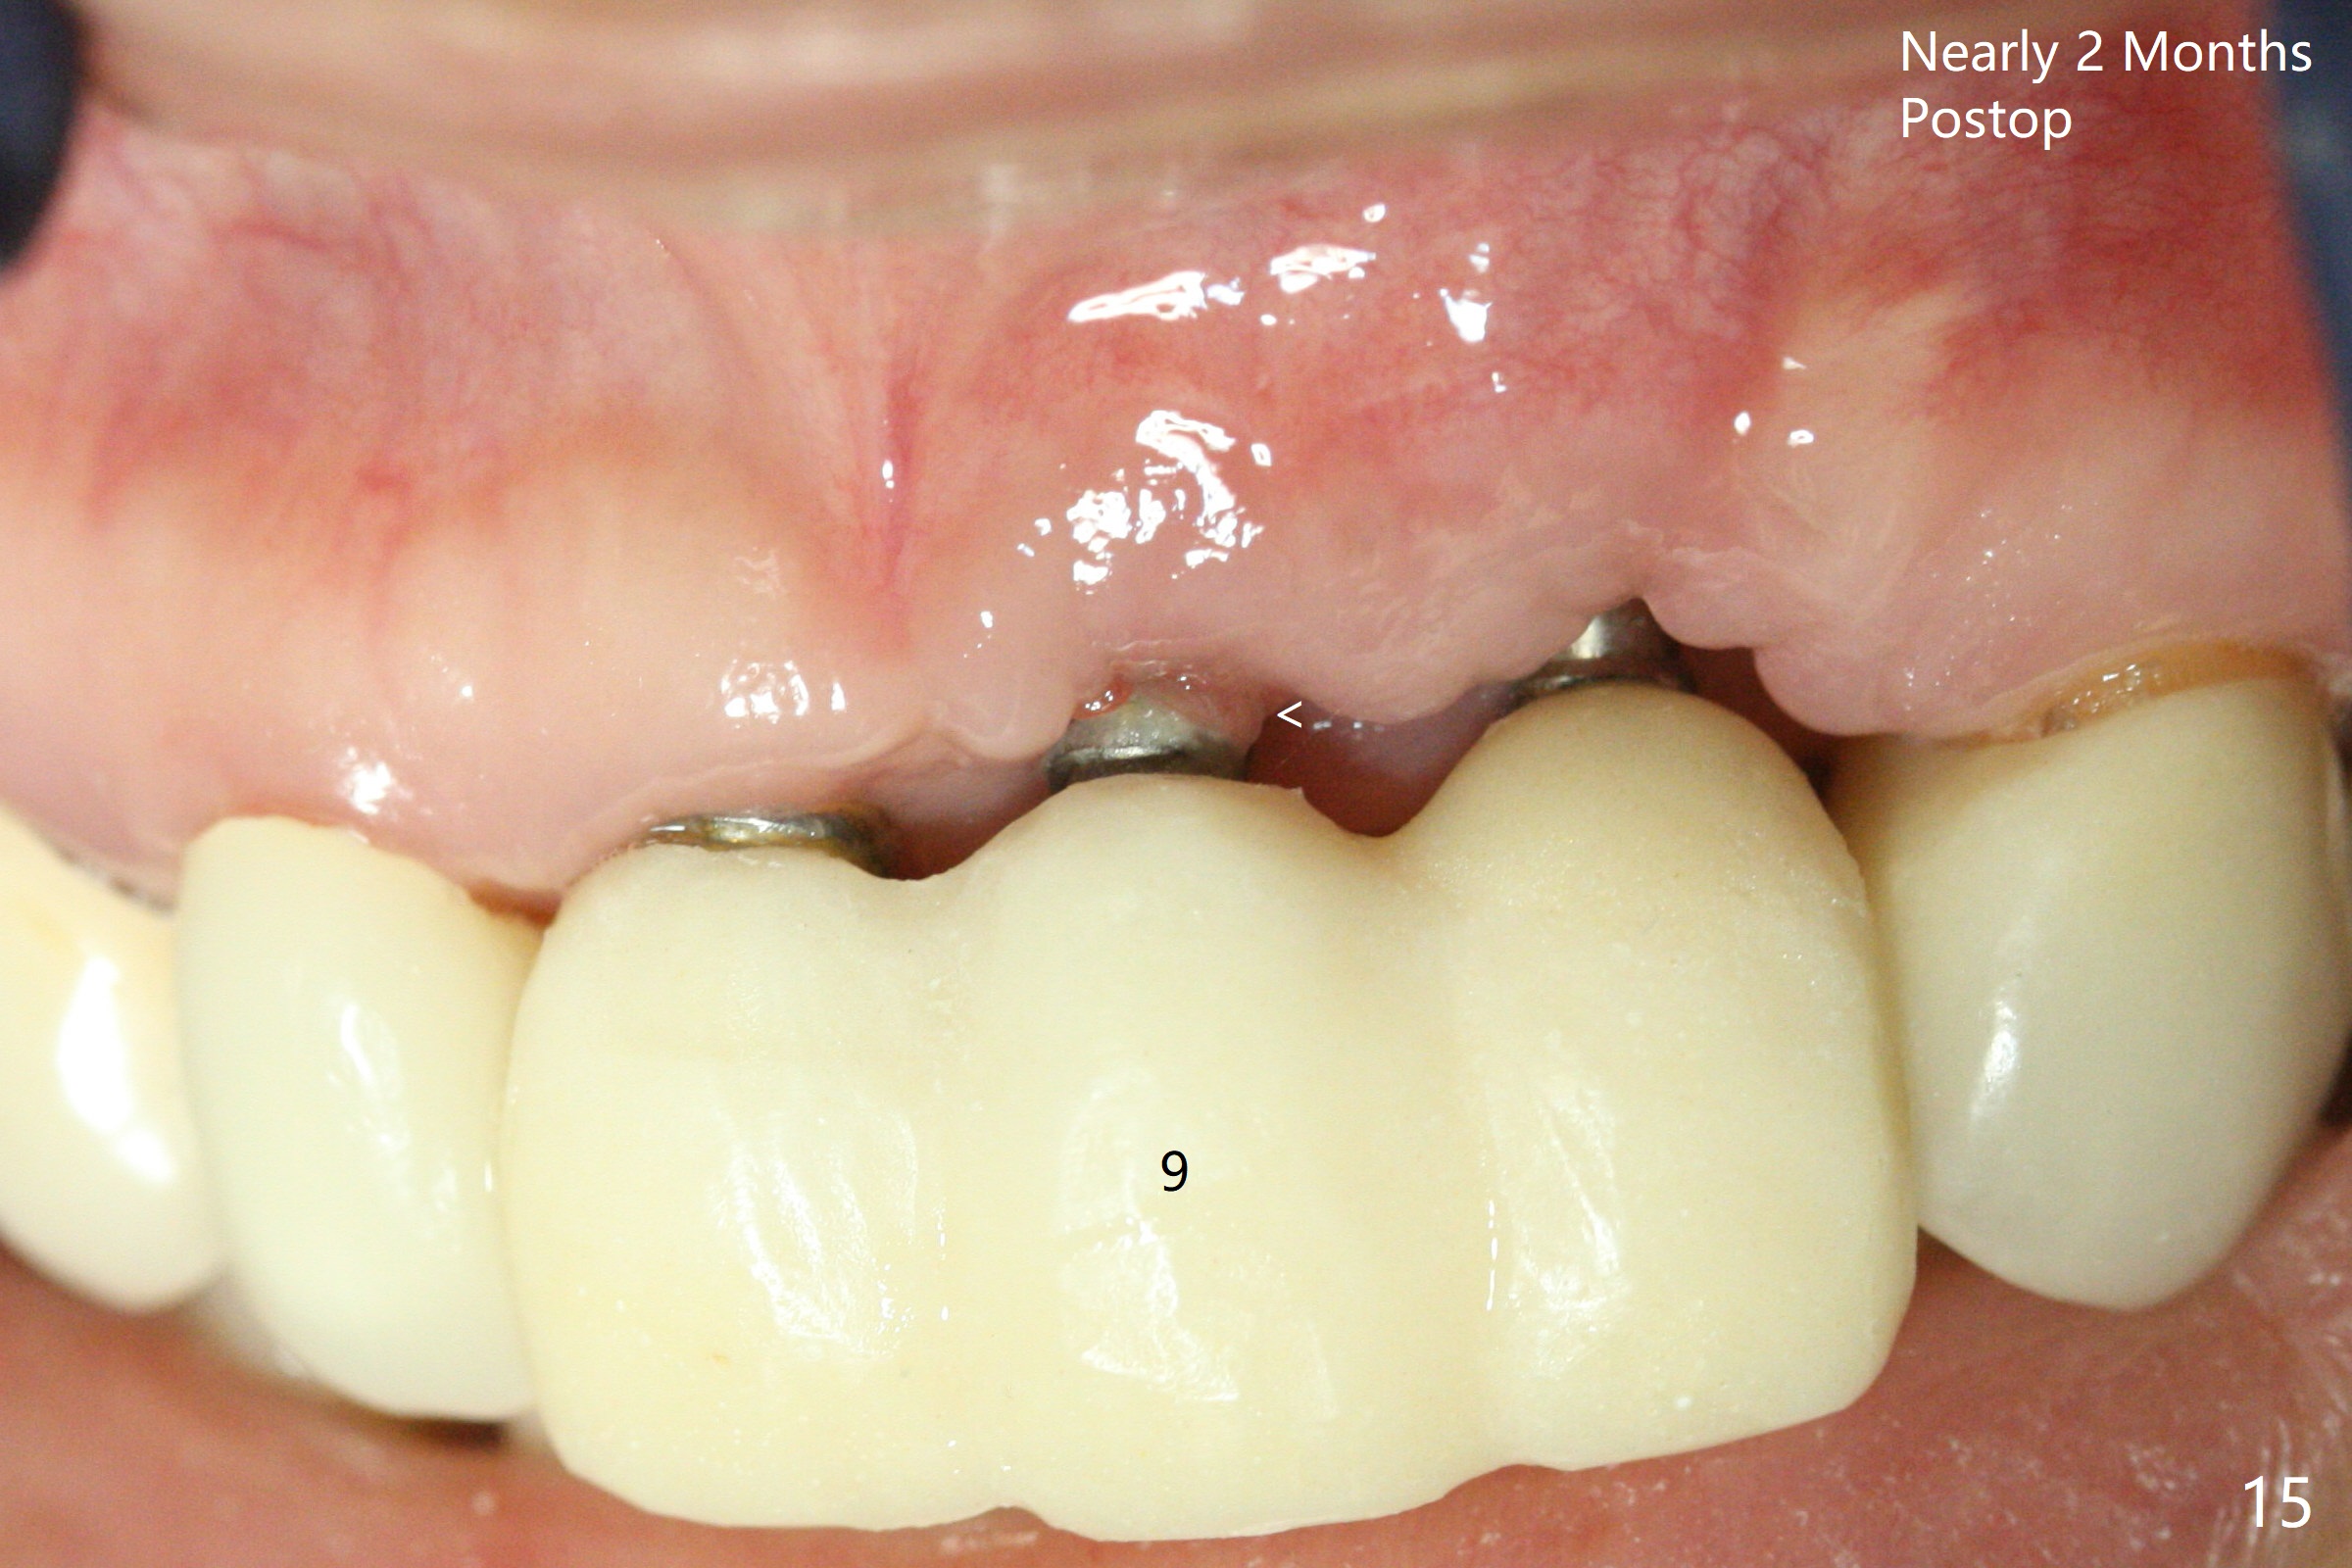

M

Incision shows exposure of microthreads at #9 and major threads at #10 due to buccal placement (Fig.1). There is bone palatal to the implant at #10 (Fig.2 P), to which a new implant will move. After implant removal, a narrower 1-piece implant (2.5x14(4) mm) is placed palatally at #10 (Fig.3,4) in combination of guide and free hand. At the site of #9 after implant removal, the guide is not used; a 3x17 mm angled 1-piece implant is placed with bad trajectory (Fig.5,6). After re-adjustment (Fig.7), the implant is placed at the right orientation (Fig.8). It appears that the guide is helpful. Allograft is placed mainly buccally (Fig.9,10 *), followed by a piece of collagen membrane (Fig.11). After tension release, flaps are approximated (Fig.12). The buccal gingiva at #9 and 10 recede nearly 2 months postop (Fig.13). Less recession at #9 is associated with more inflammation (Fig.14). The margin of the provisional is adjusted for gingival margin down growth and easy self cleaning with Water Pik (Fig.15). One month later, the gingival inflammation reduces, while there is no obvious buccal collapse (Fig.16,17). Impression is taken after laser gingivectomy nearly 4 months postop (Fig.18). While the gingiva around the implant at #9 is inflamed (periimplantitis?), the gingival cuff at #10 is well formed 5.5 months postop immediately before cementation (Fig.19). The buccal concavity at #10 is minimal (Fig.20). The gingival inflammation at #9 will be hopefully resolved after cementation of the final restorations (Fig.21). There appears to be new bone formation around the coronal implant threads 5.5 months postop (immediately post cementation, Fig.22). The microthreads at #9 may be not covered by the bone, the reason for the gingival erythema. The redness at #10 is asymptomatic 5.5 months post cementation (Fig.23). 粘固后两年牙槽嵴骨质并没有再生(图二十四),说明第一术中植体必须植入骨下(基台部分要长,否则难于修复),第二牙槽嵴处不应该有压力,植入2.5毫米植体,最后钻头应该是2.5毫米,骨下1-3毫米(尝试项目)。